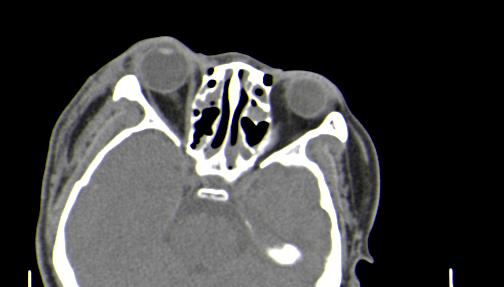

以下是引用皎皎白驹在2006-11-29 8:48:00的发言:[br]影像表现:双侧筛窦和上颌窦、鼻腔内均密度增高,右侧视神经增粗、弯曲,左筛窦顶部筛板及右侧纸板近视神经孔区可见骨折线。[br]结合临床表现考虑:右侧筛窦纸板近视神经孔区骨折致右侧视神经损伤。最好做个眼眶冠状扫描,更明确右侧视神经管是否狭窄。

以下是引用w_jianhua在2006-11-29 10:07:00的发言:[br]影像表现:双侧筛窦和上颌窦、鼻腔内均密度增高,右侧视神经增粗、弯曲,左筛窦顶部筛板及右侧纸板近视神经孔区可见骨折线。[br]结合临床表现考虑:右侧筛窦纸板近视神经孔区骨折致右侧视神经损伤。最好做个眼眶冠状扫描,更明确右侧视神经管是否狭窄。 [br] [br]支持[br]

以下是引用守望可可西里在2006-11-29 9:46:00的发言:[br][quote]以下是引用皎皎白驹在2006-11-29 8:48:00的发言:[br]影像表现:双侧筛窦和上颌窦、鼻腔内均密度增高,右侧视神经增粗、弯曲,左筛窦顶部筛板及右侧纸板近视神经孔区可见骨折线。[br]结合临床表现考虑:右侧筛窦纸板近视神经孔区骨折致右侧视神经损伤。最好做个眼眶冠状扫描,更明确右侧视神经管是否狭窄。